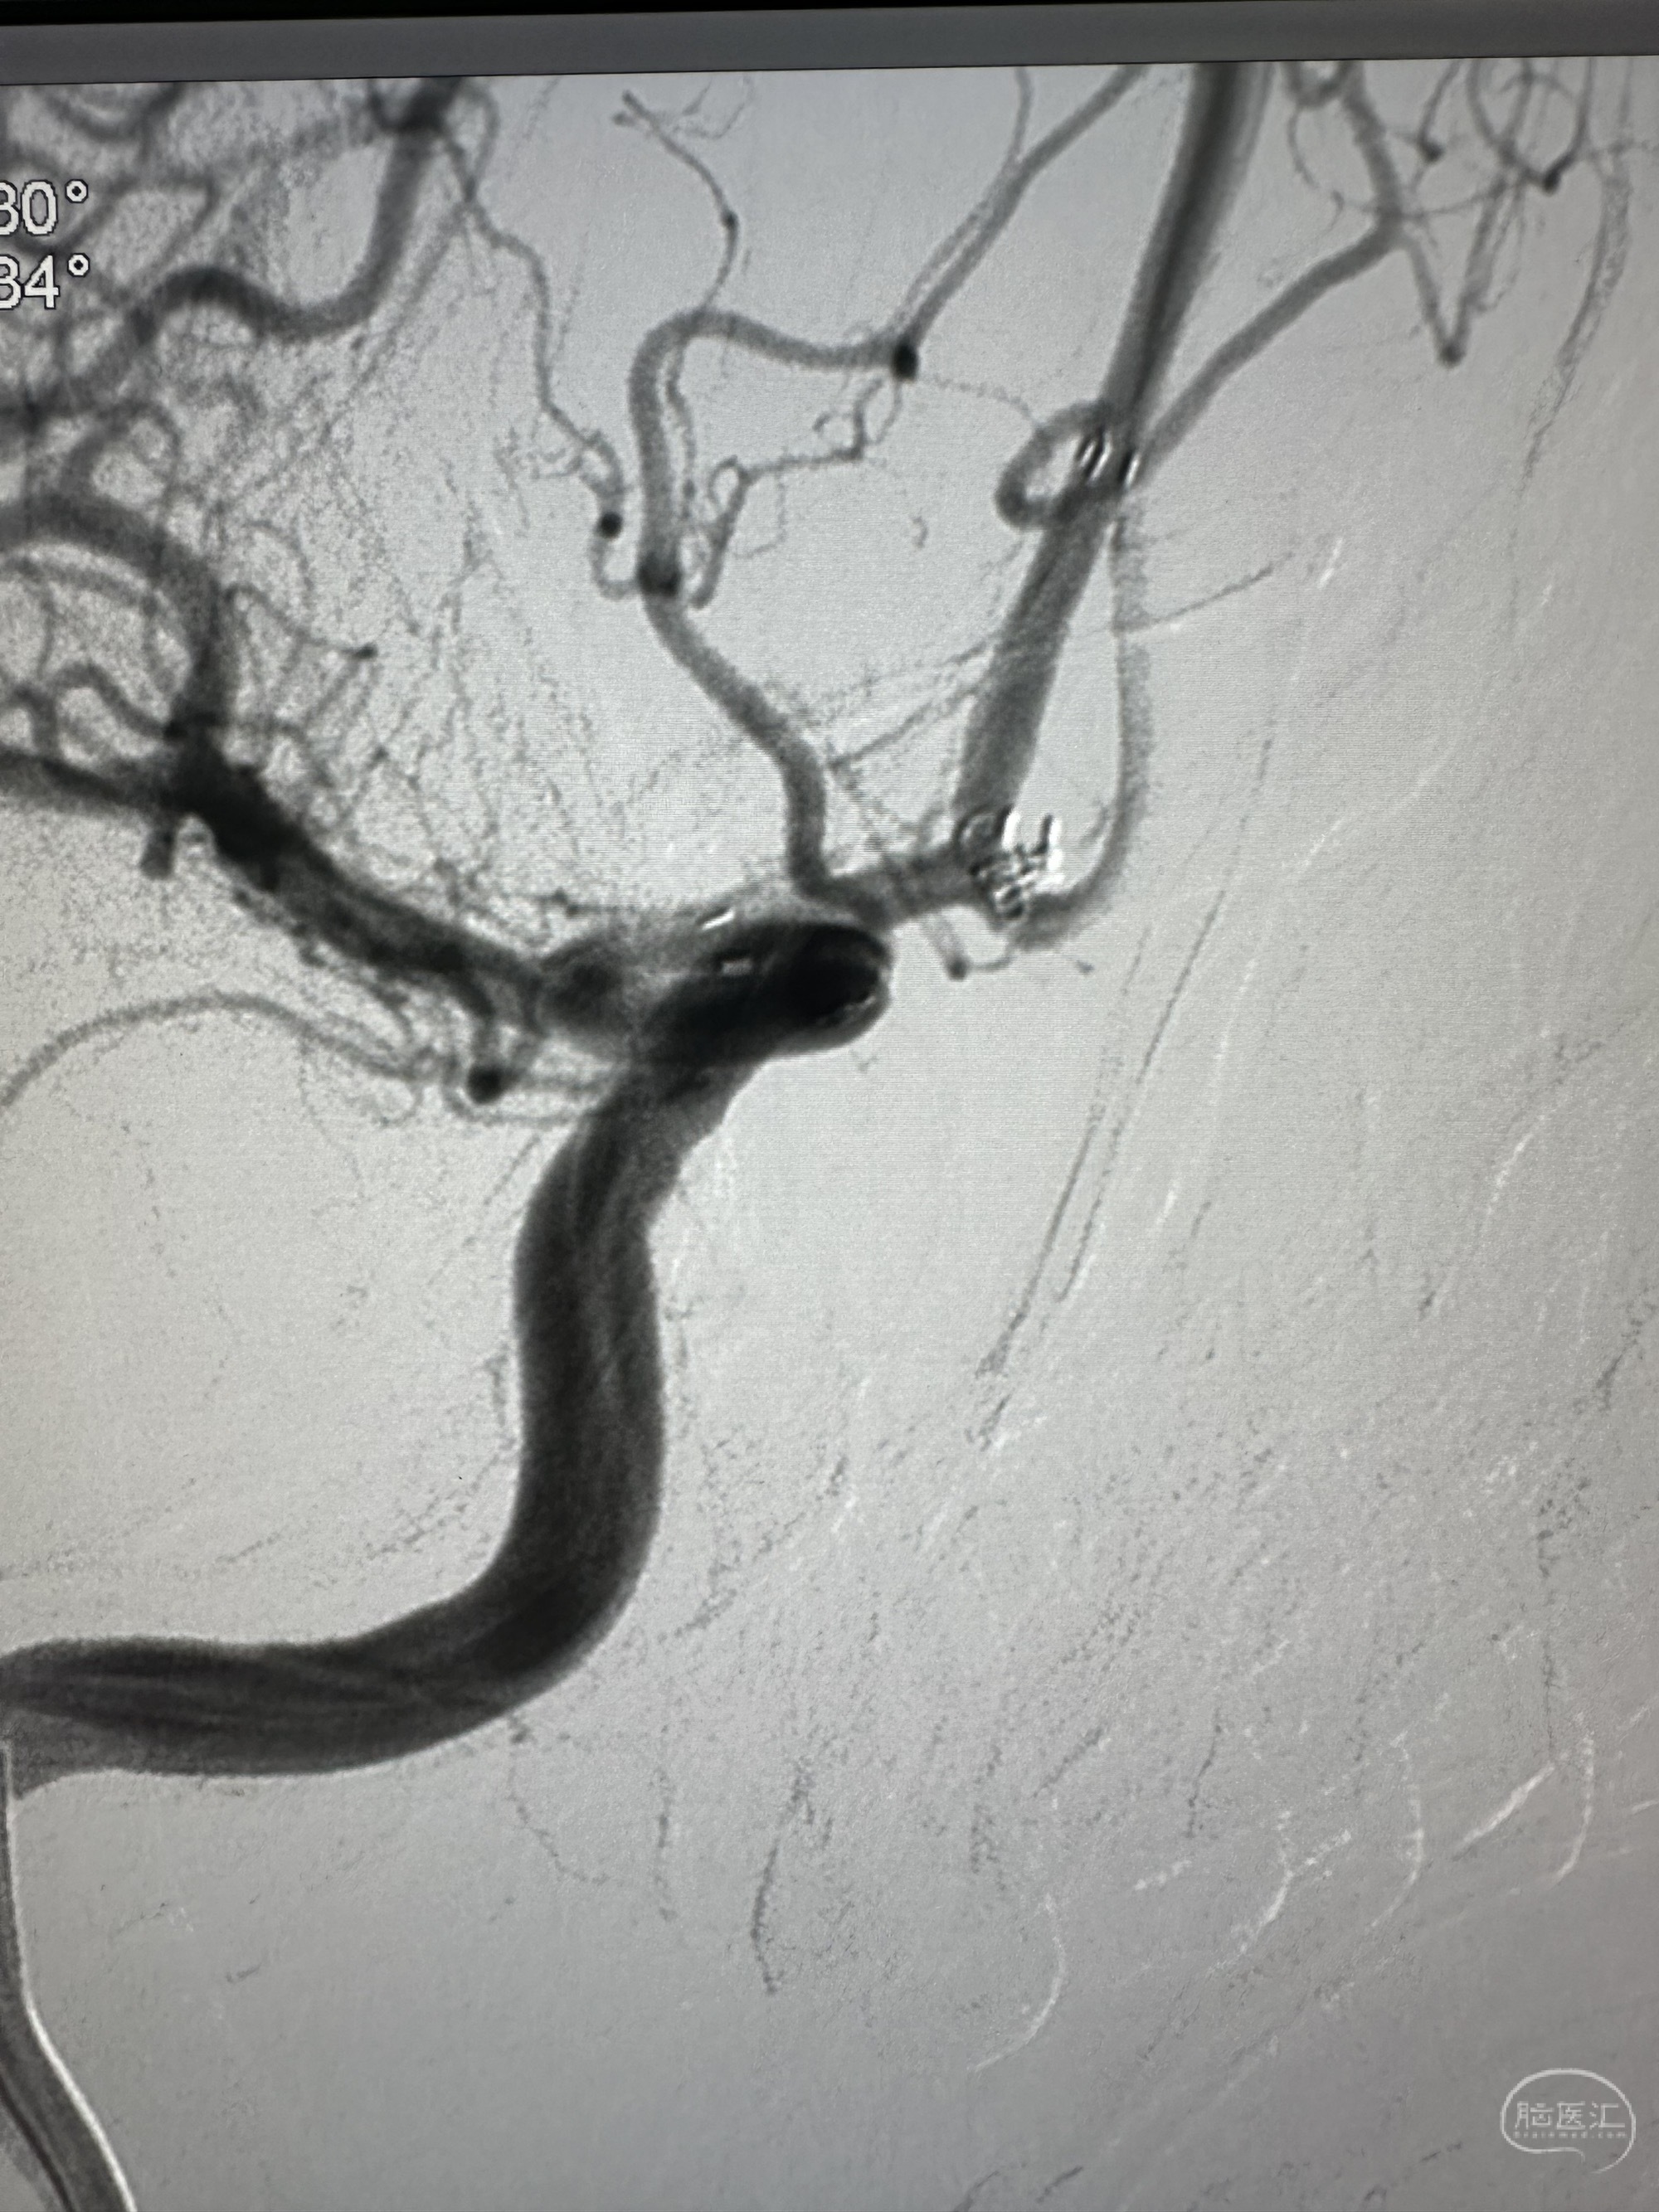

右侧颈内动脉造影感觉前交通有一个

侧位

对侧造影